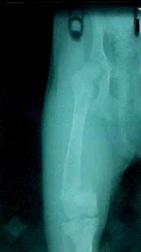

Canina: 4 luni mascul, rasa Collie

Animalul a fost lovit de o masina. De atunci schioapata de membrul posterior drept, iar coapsa dreapta a început sa se umfle. Refuza sa mai manânce.

Examen clinic

Temperatura 39,3oC, Frecventa cardiaca 113, Frecventa respiratorie 36.

schiopatura de gradul III-IV. Membrul este tumefiat, dureros si usor mai scurt decât congenerul. În general animalul refuza sa se deplaseze.

La palpatia coapsei se simte o tumefactie elastica, uneori crepitatie.

Cerinte suplimentare

Diagnostic – fractura femurala închisa , completa, simpla, epifizara (EPIFIZIOLIZĂ)

Prognostic – favorabil

Tratament – Osteosinteza cu fixatori externi (reducerea închisa a focarului de fractura)

Presupune traversarea unor tije filetate sau nu (Kirscher sau Steinmann) prin fragmentele de fractura. La exterior aceste tije vor fi fixate prin inele Ilizarov sau bare de conexiune (paste autopolimerizabile, placi metalice perforate, tije metalice cu dispozitive de prindere a broselor Steinmann sau Kirscher). Se trece: